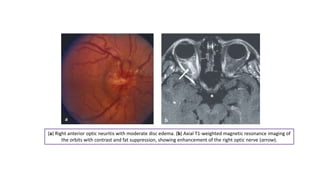

(a) Right anterior optic neuritis with moderate disc edema. (b) Axial T1-weighted magnetic resonance imaging of

the orbits with contrast and fat suppression, showing enhancement of the right optic nerve (arrow).

(a) Right anterioroptic neuritis with moderate disc edema. (b) Axial T1-weighted magnetic resonance imaging of the orbits with contrast and fat suppression, showing enhancement of the right optic nerve (arrow).